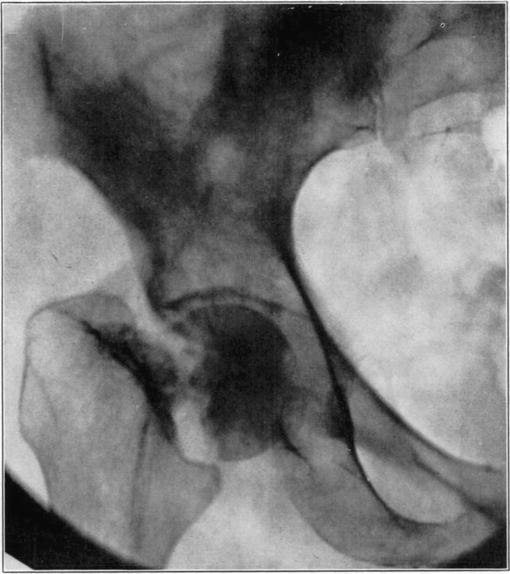

Bone Necrosis in Joint Fractures

Necrosis of bone may also occur in fractures bordering on joints from injury to the blood vessels to a large part or all of the joint fragment. It undergoes either partial or total necrosis. The condition may be met with in intracapsular fractures of the neck of the femur, of the capitellum humeri, of the carpal navicular, of the head of the radius and of the neck of the astragalus, and it always follows complete detachment of small fragments in intra-articular fractures.

Necrosis of the proximal fragment in complete intracapsular fracture of the neck of the femur occurs in a not inconsiderable percentage of the cases. Santos [7] has recently completed a detailed study which has thrown light on many aspects of the condition. A summary of his report follows: Necrosis may occur in fractures at any age, and although relatively more frequent in older persons, it is often absent in them. This may sometimes be because of blood reaching it by way of vessels in the untorn periosteum. The vessels of the ligamentum teres may supply adequate blood to keep the head alive even in the aged.

Death of the proximal fragment predisposes to non-union, but union occurs in a considerable percentage of the cases with a dead head in which there is impaction of fragments or in which there is efficient reduction and fixation of fragments, the best results apparently being obtained from the closed abduction method of Whitman. At the end of the period of immobilization the distal living fragment usually shows roentgen-ray signs of reduced density due to atrophy of disuse, but the necrotic head which cannot atrophy casts practically as even and heavy a shadow as at the time of fracture. This usually makes it possible to diagnose necrosis roentgenologically at this stage.

If bony union occurs the head is gradually invaded by the ingrowth of tissue from the distal fragment and sometimes from the hypertrophied round ligament. The necrotic marrow is replaced by vascular connective tissue and eventually by bone marrow, but the necrotic bone is much more slowly absorbed and replaced by a variable amount of irregularly arranged living bone. The necrotic cartilage is slowly absorbed and replaced by fibrous tissue, fibro-cartilage, and to some extent eventually by new hyaline cartilage. If too much weight is borne on the head before it has been transformed into new bone, its weight-bearing portion may collapse with a resultant deformity and a poor functional result, but this may be averted by prolonged avoidance of weight-bearing. The functional stimulation which comes from motion of the limb without weight-bearing is sufficient to hasten transformation of the head.

Necrotic femoral head casting heavier shadow than surrounding atrophied living bone.

Roentgenogram of slice of excised head in Fig. 7, showing old necrotic bony trabeculae still undisturbed.